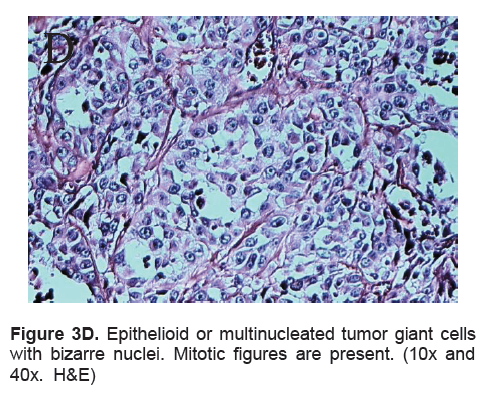

The right lobe measured 8.3 x 6.0 x 4.3 cm, and weighed 119.5 grams with a tan brown surface covered with fibrous tags (Figure 3A). Cut sections showed an ovoid mass, 6.7 x 5.2 cm in greatest dimensions, with a thin capsule and yellow-tan, gritty to mucoid cut surface with areas of hemorrhage and necrosis. The tumor infiltrated and replaced normal thyroid parenchyma and was surrounded by a thin capsular rim. Tissue sections of the right lobe revealed an infiltrative tumor composed of an admixture of pleomorphic cells, spindle cells and occasional tumor giant cells (Figure 3B). There were small areas showing reminiscent papillary or microfollicle pattern, while some areas showed large epithelioid or multinucleated tumor cells with bizarre nuclei (Figure 3C). Capsular (Figure 3D) and vascular (Figure 3F) invasion were present with extensive tumor necrosis. The uninvolved right and left lobes showed multinodular colloid goiter with lymphocytic thyroiditis. It was signed out as an Anaplastic (undifferentiated) thyroid carcinoma of the right lobe.

Click here to download Figure 3D

Figure 3D. Epithelioid or multinucleated tumor giant cells with bizarre nuclei. Mitotic figures are present. (10x and 40x. H&E)